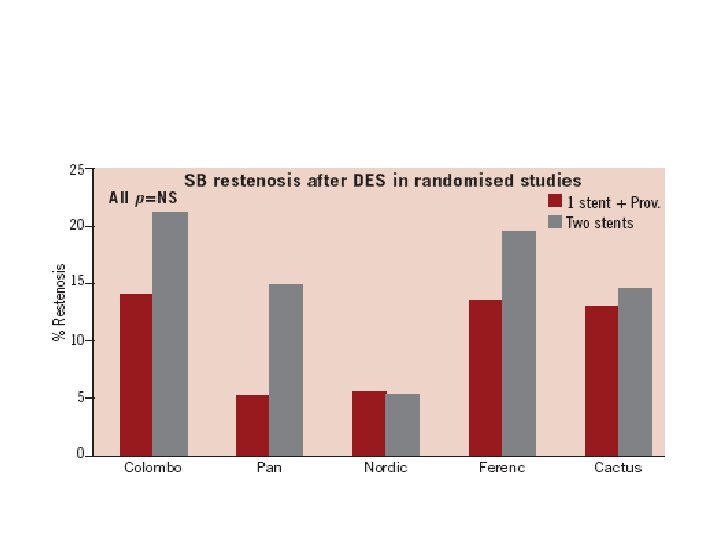

One vs two stents • • • Important trials NORDIC 2 BBC CACTUS

1. Nordic I: provisional T stenting as good as systematic side branch stenting 2. Nordic II: Culotte better than Crush 3. Cactus: provisional T stenting not worse than crush 4. BBC ONE: step wise approach with provisional T stenting better than initial complex procedures 5. Bad Krozingen: no difference provisional vs systematic T 6. Double Kiss Crush Study: DK Crush better than conv. crush Steigen Circulation 2006; 114: 1955; Erglis TCT 2008; Hildick-Smith TCT 200 Ferenc EHJ 2009; Chen JInterv Cardiol 2009; 22: 121 -27